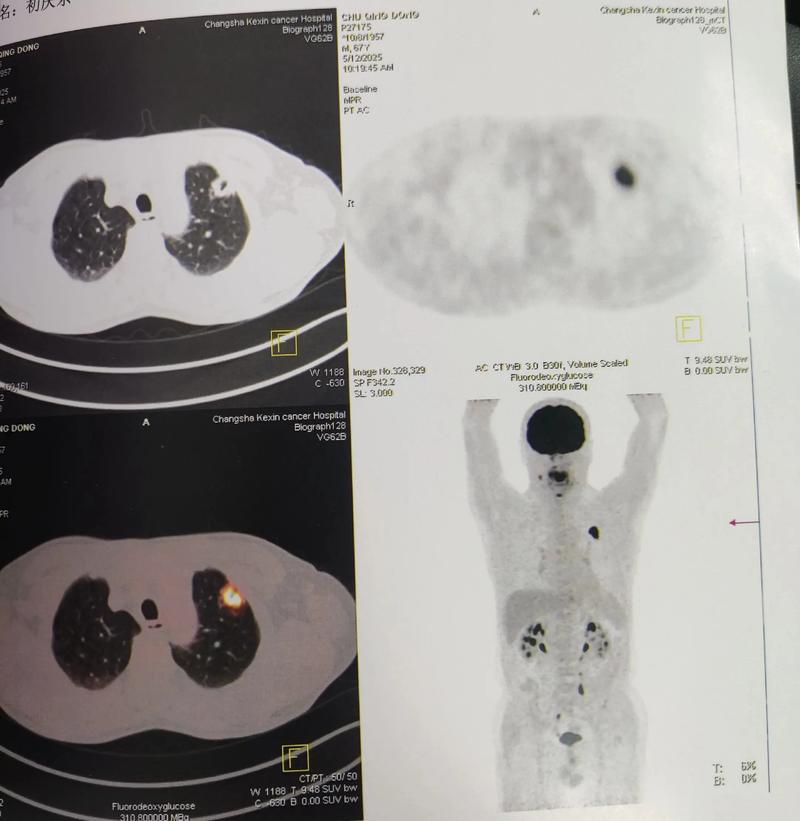

- PET-CT的角色: 在急性期,PET-CT的角色不是“看”梗塞本身,而是“看”脑组织的功能状态和代谢情况,通过PET-CT灌注成像,可以评估脑梗塞区域的血流供应情况,判断是否存在“缺血半暗带”(Ischemic Penumbra),缺血半暗带是梗塞核心周围处于缺血但尚未坏死、仍有抢救潜能的脑组织,识别出这部分组织对于医生决定是否进行溶栓或取栓治疗至关重要。

- 检查方法: 使用18F-FDG(氟代脱氧葡萄糖)作为示踪剂。

- 原理: 葡萄糖是大脑最主要的能量来源,18F-FDG PET可以显示大脑各个区域的葡萄糖消耗情况,从而反映神经元的代谢活性。

- 在脑梗塞中的应用:

- 区分梗死核心与缺血半暗带(急性期): 梗死核心区因细胞坏死,FDG摄取极低或缺如,而缺血半暗带区虽然血流减少,但细胞尚未死亡,为了维持功能,会表现出“过度摄取”FDG的现象(即Luxury Perfusion),这为治疗决策提供了关键信息。

这是PET-CT在神经领域一个极其重要的应用,约30%的脑梗塞患者常规检查找不到明确原因,这些被称为“隐源性卒中”,PET-CT可以帮助寻找“隐藏的”病因。

- 血管炎: 使用18F-FDG PET可以清晰地显示受累血管壁的异常高代谢(炎性反应),这对于诊断和评估大血管炎(如巨细胞动脉炎)引起的脑梗塞非常有帮助。

- 心脏来源的栓塞: 对于怀疑心源性栓塞(如房颤)但常规检查难以证实的患者,18F-FDG PET可以发现心脏瓣膜、心房或大血管的感染性心内膜炎或恶性肿瘤(如粘液瘤),这些是潜在的栓子来源。

- 肿瘤: 肿瘤细胞通常葡萄糖代谢异常旺盛,在18F-FDG PET上表现为明显的高代谢灶,这与梗塞灶的低代谢形成鲜明对比。